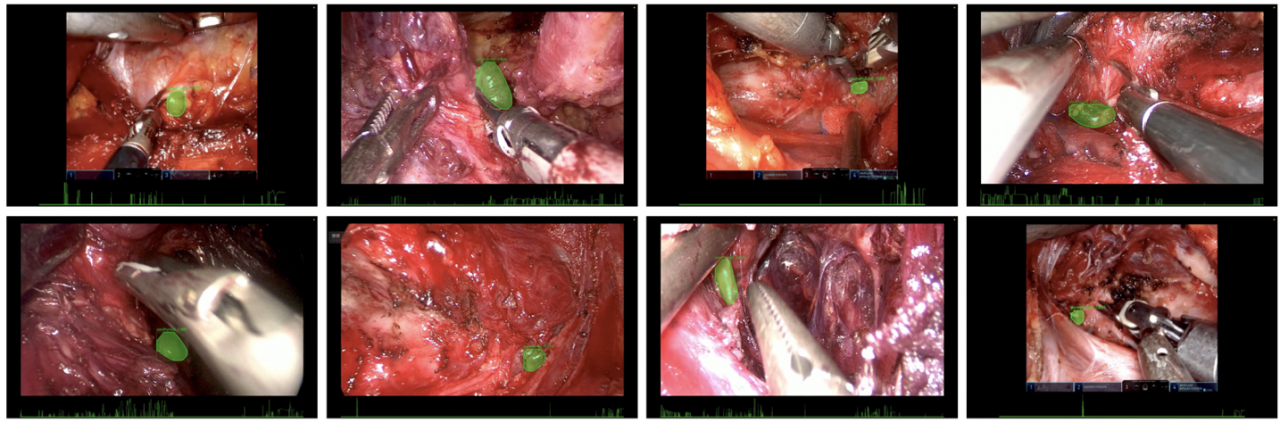

软件学院刘勇国教授团队在肌少症肌量评估研究方面取得新进展

2025-11-22

近日,信息与软件工程学院医药知识工程与智能软件实验室刘勇国教授团队在肌少症肌量评估方面取得重要研究进展,相关成果“Sarcopenia Assessment Model Based on Dual-Sourc...